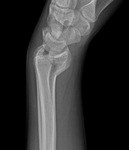

Radiografia posteroanterior mostrando a consolidação viciosa do rádio distal, com encurtamento significativo do rádio e alongamento relativo da ulna

Do acervo do Dr. Chaitanya S. Mudgal